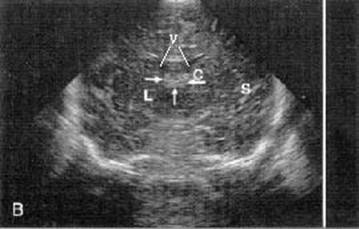

Normal Coronal HUS. V: lateral ventricles, C: caudate head, Arrows: choroid

plexus,

L: lentiform nucleus, S: Sylvian

fissure.